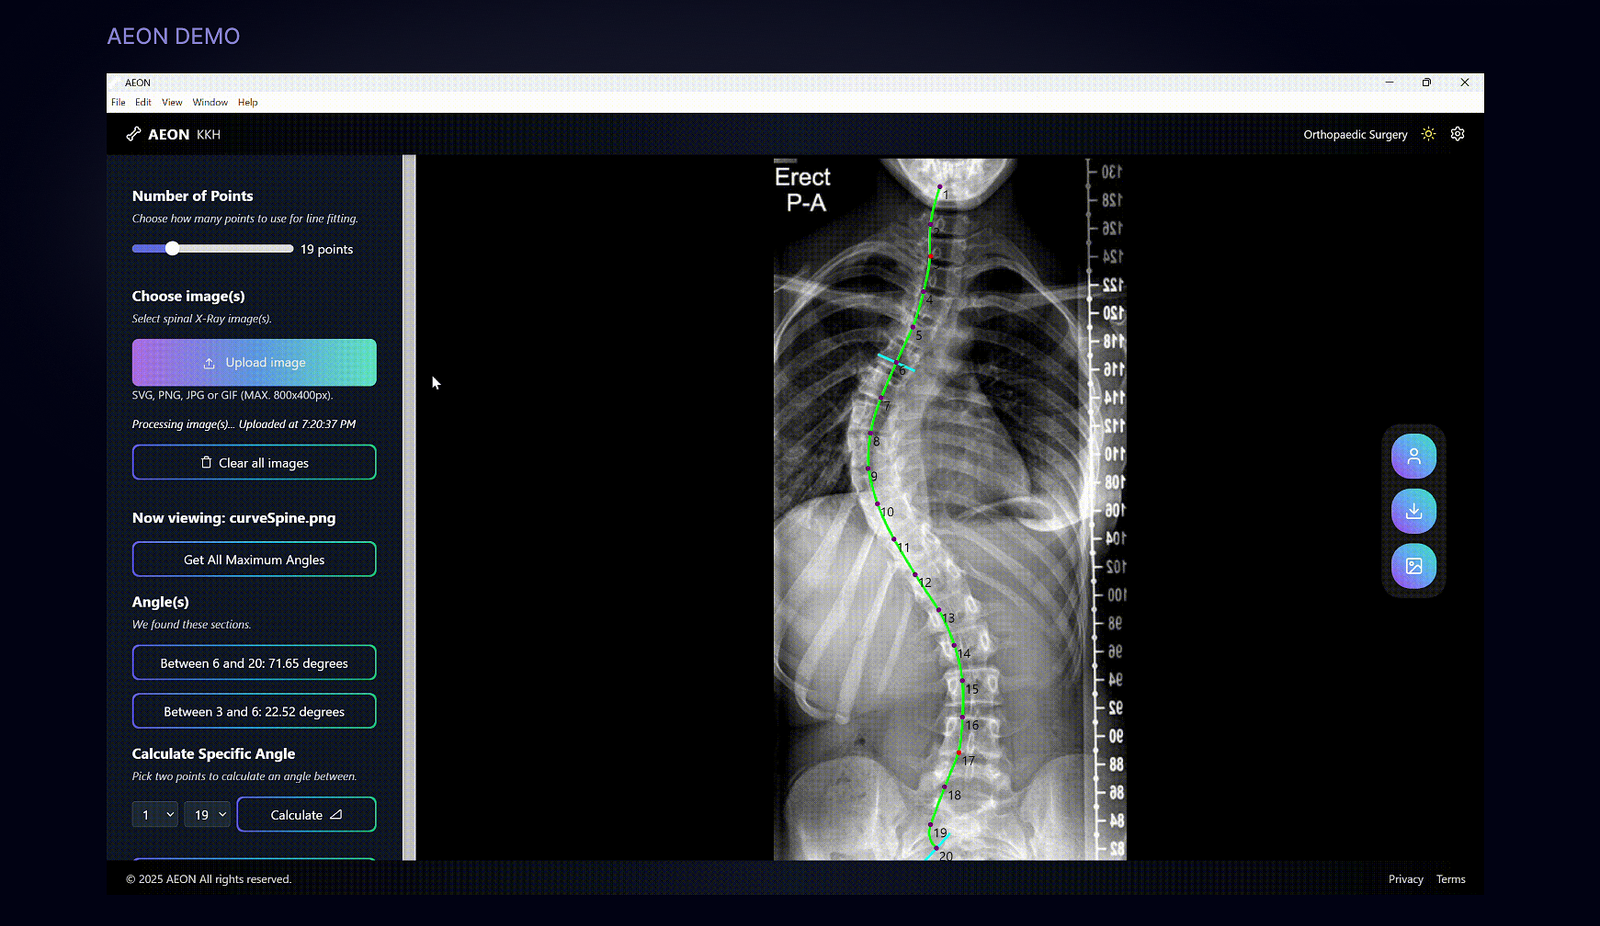

Automated X-Ray Analysis

Detects key anatomical landmarks and analyzes pediatric spinal X-rays to assist in measuring curvature angles and deformities.

Fast & Efficient Measurements

Generates measurements in ~3 seconds, significantly reducing the time required for manual analysis.

Accurate & Consistent Results

Achieves >90% reproducibility comparable to consultant measurements, while being EHR-agnostic and easy to integrate into clinical workflows.